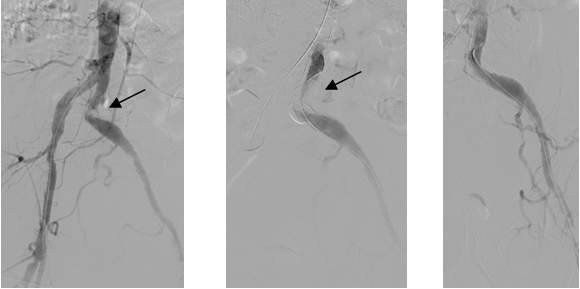

Figure 4. Primary stenting of an 80-90% stenosis on the distal portion of the left common iliac artery distal stenosis. Left and middle panel: stenosis is indicated by the arrow. Contrast medium was given from the aorta proximal to the stenosis (left panel) or the left common iliac artery distal from the stenosis.

Due to technical reasons (antegrade or retrograde puncture, contralateral or ipsilateral puncture, femoral or brachial puncture), prognosis and risks, three types of levels are distinguished: iliac (Figure 4), femoro-popliteal (Figure 5) and crural (infragenual) (Figure 6) endovascular therapy. The latter two composes the infrainguinal group. PTA and stent placement are usually technically easier (with the exception of long occlusions), have a longer patency and carry lower risk in the iliac group compared to the other two groups. Patency following crural PTA is the worse and carries the highest risk, therefore, it is usually indicated only in Fontaine stages III and IV. The number of amputation per capita in Hungary is larger than that in most other European countries. In patients with gangrene and diabetes mellitus, crural PTA may save a large number of amputations. In case of successful PTA, limb salvage rate is considerably higher than crural patency rate, since perfusion needed for a healing ulcer or gangrene is considerably higher than for the basic functions (collateral arteries may be sufficient for such purpose). Subintimal PTA is performed more and more frequently: when luminal recanalisation is technically not possible, intentional dissection is done using the hydrophilic guidewire along the occluded segment; then, distally to the occlusion, the guidewire is directed back to the normal lumen and a new channel is formed along the normal lumen–dissected channel–normal lumen route (Figure 5).

Figure 6. Crural PTA. Left panel: the only crural vessel filling is the peroneal artery; the posterior tibial artery is filled only in the proximal segment; the plantar arch in its continuation is also filled. Middle panel: successful recanalisation of the posterior tibial artery was performed using the guidewire (dashed arrow). Right panel: following balloon dilation, posterior tibial artery is well filled (arrows).